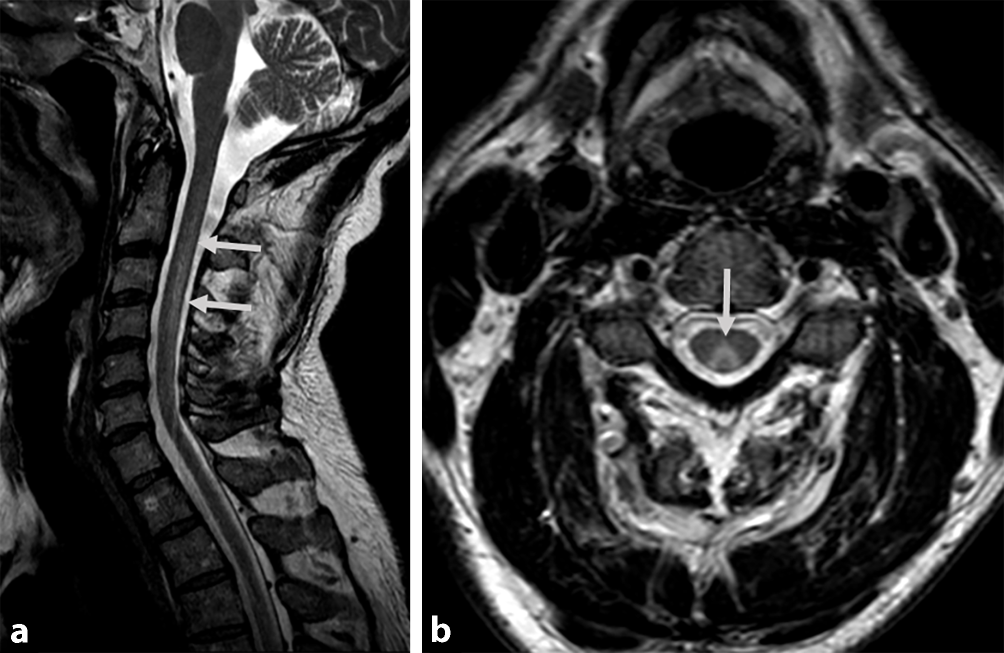

Ein 45-jähriger Mann wurde uns mit vier Wochen zuvor erstmals aufgetretenen, progredienten Akroparästhesien und symmetrisch aufsteigenden Paresen vorgestellt. Er berichtete auf Nachfrage über die Inhalation von vier mit Lachgas gefüllten Luftballons sieben Wochen zuvor. Es bestand eine ausgewogene Ernährung, eine spezielle Diät wurde nicht eingehalten. In der neurologischen Untersuchung fielen eine sensible Ataxie mit distal symmetrischer Hypästhesie und eine Pallhypästhesie bei erhaltenem Temperaturempfinden auf. Die Achillessehenenreflexe waren ausgefallen und es zeigten sich Paresen der distalen Extremitätenmuskeln. Es fand sich keine autonome Dysfunktion und keine Hirnnervenausfälle. Die Liquordiagnostik erbrachte unauffällige Befunde mit normwertigem Eiweißgehalt, normwertiger Zellzahl sowie unauffälliger Lactat- und Glukosekonzentration, sodass kein Anhalt für eine Infektion bestand. Eine Borrelienserologie war unauffällig. Gangliosidantikörper (GM1, GQ1b, und GD1b, jeweils IgG und IgM) waren im Serum nicht nachweisbar. Labordiagnostisch fiel eine leicht reduzierte Erythrozytenzahl von 4,2 T/l (Normbereich 4,3–5,75 T/l) bei leichter hyperchromer (MCH 34 pg; Normbereich 27–33,5 pg) Makrozytose (MCV 102 fl; Normbereich 80–99 fl) bei normwertiger Hämoglobinkonzentration auf. Die Vitamin‑B12- und Holotranscobalamin-Serumspiegel lagen im Normbereich. Allerdings fiel eine schwere Hyperhomocysteinämie von 108,12 µmol/l (Normbereich 3,2–10,7 µmol/l) auf. Die Elektroneurographie erbrachte den Befund einer axonal-demyelinisierenden Polyneuropathie mit verlängerten F‑Wellen-Latenzen, verlängerten distal motorischen Latenzen, herabgesetzten Nervenleitgeschwindigkeiten und reduzierten Muskelsummenaktionspotenzialen (Tab. 1). Eine zervikale spinale Magnetresonanztomographie zeigte T2-Hyperintensitäten der Hinterstränge in den Höhen C2 bis C7, welche in der sagittalen Bildgebung V‑förmig zur Darstellung kamen (Abb. 1a, b).

Abb. 1

T2-gewichtete zervikale MRT. a Sagittale, b axiale MRT mit V‑förmigen Hyperintensitäten der Hinterstränge (Pfeile)

Die Inhalation von Lachgas führt zu einem metabolischen Vitamin‑B12-Mangel, welcher neben Blutbildveränderungen zu einem neurologischen Syndrom mit Polyneuropathie und Hinterstrangaffektion führen kann [7]. Die symmetrischen Veränderungen der Hinterstränge werden als „inverted V-sign“ beschrieben [3]. Neurographisch können sowohl Zeichen eines axonalen Schadens als auch einer Demyelinisierung nachweisbar sein. Die routinemäßig bestimmten Vitamin‑B12- und Holotranscobalamin-Serumspiegel sind weniger sensitiv als die Bestimmung des Homocysteinspiegels und der Methylmalonsäure, weshalb der metabolische Vitamin‑B12-Mangel leicht übersehen werden kann [4]. Ein normaler Vitamin‑B12-Spiegel wird bei 20–40 % der Patienten beschrieben. Auf die Bestimmung von Methylmalonsäure wurde verzichtet, weil die Bestimmung von Holotranscobalamin und Methylmalonsäure in etwa den gleichen Stellenwert bei Patienten mit Lachgasinhalation einnehmen (Methylmalonsäure 93,8 % vs. Homocystein 90,3 % auffällige Werte; [4]). Ein vorbestehender Vitamn‑B12-Mangel stellt dabei ein Risikofaktor für die Entwicklung neurologischer Symptome nach Lachgasinhalation dar [6]. Der zugrunde liegende Pathomechanismus ist eine durch Lachgas induzierte Oxidation des Cobalt-Zentralions des biologisch aktiven Methylcobalamins und Inaktivierung von Adenosylcobalamin, welche zu einer Inhibition der Enzyme Methylmalonyl-CoA-Mutase und Methioninsynthase führt, deren Substrate (Methylmalonsäure bzw. Homocystein) dann akkumulieren. Die Neurotoxizität ist unter anderem Folge eines hierdurch verursachten Methioninmangels, der eine Myelinisierungsstörung verursacht [1]. Zu beachten ist, dass die klinische Präsentation und die neurographischen Veränderungen einem Guillain-Barré-Syndrom ähneln können [5]. Der vorgestellte Fall unterstreicht daher die Bedeutung einer sorgfältigen Suchtmittelanamnese bei Patienten mit subakut aufgetretener Polyneuropathie.